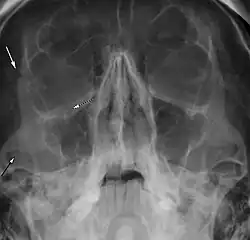

| Right zygomaticomaxillary complex fracture with disruption of the lateral orbital wall, orbital floor, zygomatic arch and maxillary sinus. | |

The zygomaticomaxillary complex fracture, also known as a quadripod fracture, quadramalar fracture, and formerly referred to as a tripod fracture or trimalar fracture, has four components, three of which are directly related to connections between the zygoma and the face, and the fourth being the orbital floor. Its specific locations are the lateral orbital wall (at its superior junction with the zygomaticofrontal suture or its inferior junction with the zygomaticosphenoid suture at the sphenoid greater wing), separation of the maxilla and zygoma at the anterior maxilla (near the zygomaticomaxillary suture), the zygomatic arch, and the orbital floor near the infraorbital canal.